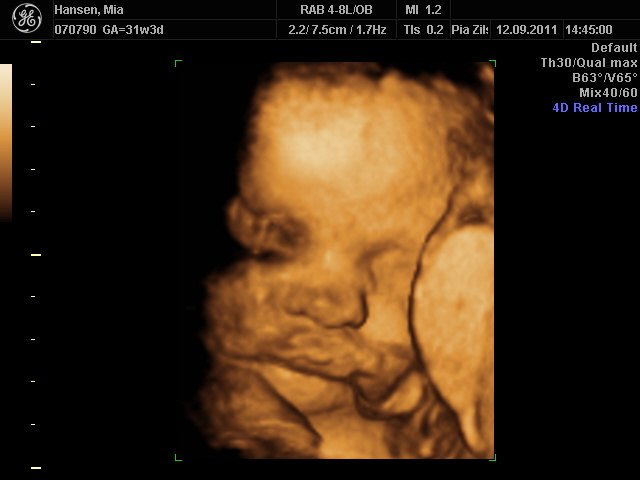

Så er vi næsten lige kommet hjem fra scanningen i københavn

Hold da helt op hvor hun kunne charme sin mor & far, hun er bare så lækker, hun lå lige som hun skulle for at få gode billeder af hende

(med hovedet nedad)

Hun er stadigvæk en rigtig putterøv, men vi fik en masse smil og trut-munde af hende

hun har lange øjenvipper og hår i nakken

Åhh er bare så forelskede i hende og glæder mig bare så meget til hun kommer til verden

FANTASTISK oplevelse

Mia 31+3